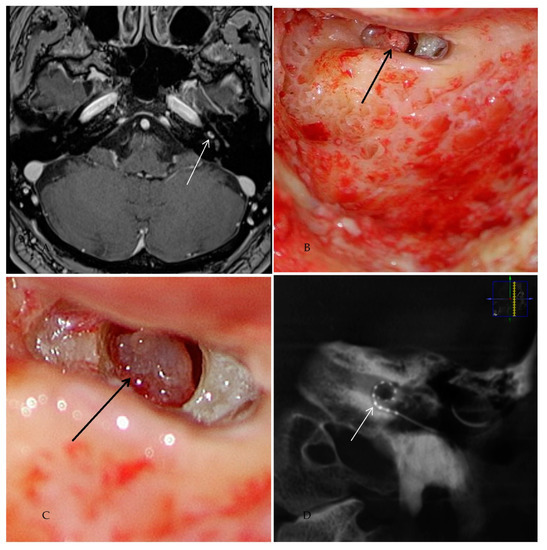

Patient #6 had intravestibular ILS (in the anterior part of the horizontal semicircular canal, Figure 5A–D). Therefore, it was necessary to use a translabyrinthine approach during tumor removal. For implantation, the round window approach was used. After surgery, the patient developed a transient facial nerve paralysis (House–Brackmann score IV) treated with intravenous prednisone, as per local SOP (dosage during surgery 250 mg; after surgery-tapering scheme down to 5 mg a day) and targeted physiotherapy. Four months after surgery, the facial nerve function was restored.

Figure 5. Case #6: cMRI images demonstrating the intravestibular schwannoma. (A,B): T1 weighted VIBE 3D with fat saturation prepulses after the intravenous administration of gadolinium. White arrow: intravestibular schwannoma in the ampulla and in the anterior part of the horizontal semicircular canal. (C,D): T2 weighted SPACE sequences. (C) Intravestibular schwannoma in the anterior part of the horizontal semicircular canal (white arrow). (D) ILS in the ampulla (white arrow).

Patient #9 had basal turn ILS. The tumor mass extended from the lateral wall to the beginning of the middle cochlear turn. Therefore, an extended cochleostomy approach was used for the tumor excision. After ILS removal, insertion of the cochlear implant electrode was performed successfully (Figure 6).

Figure 6. Case # 9: Intraoperative images demonstrating ILS-tumor resection surgery from the basal turn of the cochlea and cochlear implantation. (A) ILS in the basal turn after removing the promontory wall and bony structures around the round window (black arrow). (B) Resection of the ILS (asterisk marks the cochlear modiolus). (C) Insertion of the cochlear implant CI 612 (black arrow marks the stylet of the electrode). (D) Image after complete insertion of the electrode. The tip of the electrode can be seen in the middle turn (black arrow).